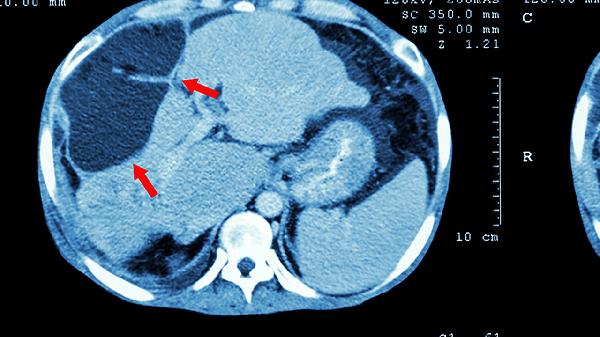

普通CT多采用4-64排探测器配置,单圈扫描仅能获得有限层数图像,心脏检查需配合心电门控且图像质量易受心率影响。空间分辨率约0.5毫米,对小于5毫米的肺结节显示能力有限。常规头部扫描辐射剂量约2mSv,虽能满足脑出血、骨折等基本诊断需求,但进行多部位扫描时累计剂量较高。在腹部检查中,普通CT对肠系膜血管显示不清,难以判断小肝癌的动脉供血特征。对于骨科三维重建,普通CT生成的图像可能出现阶梯状伪影。